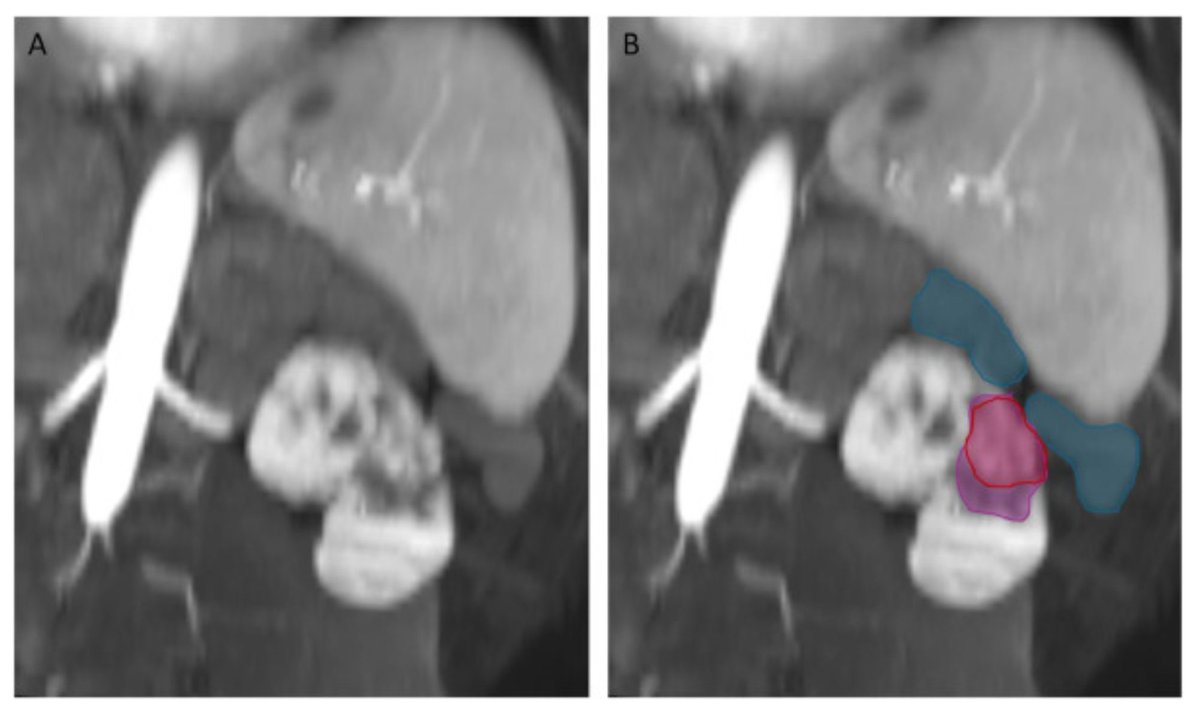

Interventional Radiology has a leading responsibility for patients with #HCC.

Congrats to my colleague @FZIslamMD for leading our latest pub, which highlights the importance of multidisciplinary management for HCC + the critical footprint of Interventional Radiology across multiple timepoints. 📝 dovepress.com/real-world-ana… @BeauToskichMD @MayoClinicFL_IR